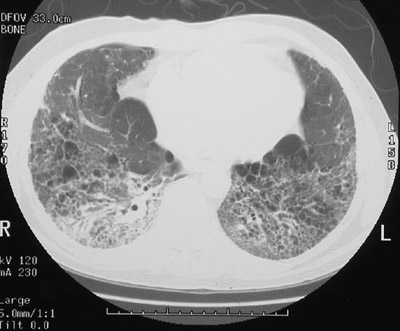

| In this chest CT scan in the "lung window" mode can be seen very prominent interstitial markings, particularly in the posterior lung bases. There are also smaller lucent areas that represent honeycomb change, a characteristic feature of usual interstitial pneumonitis (UIP), an idiopathic and progressive restrictive lung disease. Patients develop pulmonary hypertension and cor pulmonale. |